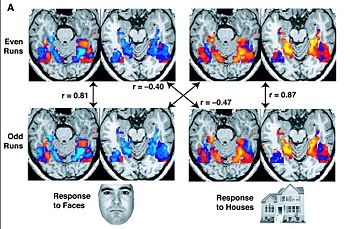

The biological basis of personality is the theory that anatomical structures located in the brain contribute to personality traits.. Tis stems from neuropsycology, which studies how the structure of the brain relates to various psychological processes and behaviors. In human beings, the frontal lobes are responsable for foresight and anticipation, and the occipital lobes are responsable for processing visual information. In addition, certain physiological functions such as hormone secretion also affect personality. Hormone testosterone is important for sociability (aggressiveness, and sexuality). Studies show that the expression of a personality trait depends on the volumen of the brain cortex it is associated with.